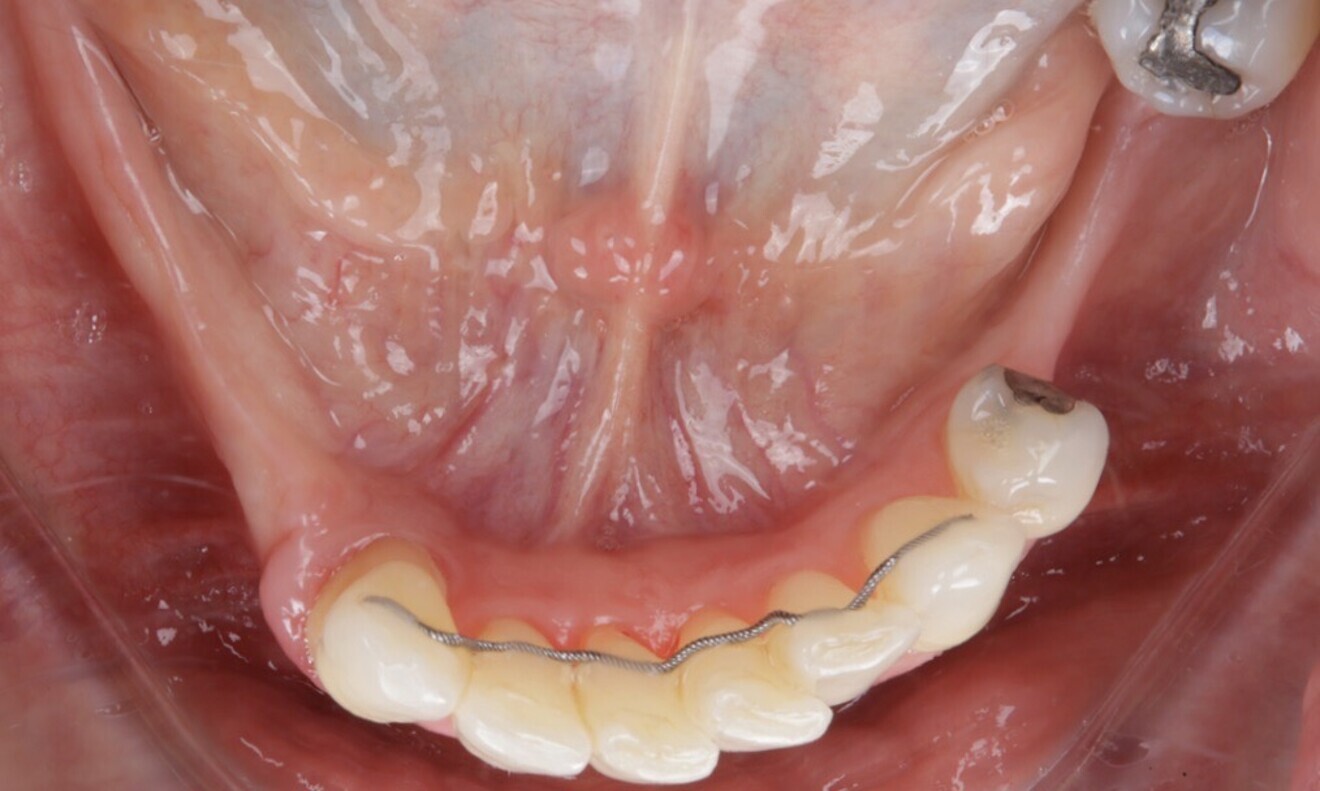

The patient wore a removable restoration in the maxillary arch and presented with anterior retainers in both the maxillary and mandibular arches owing to tooth mobility caused by periodontal disease. Teeth #15, 13, 23, 25, 27, 36, 35, 44, 45, 46 and 47 were missing. Additionally, the patient presented with several dental fillings (Figs. 4–7).

Figs. 4–7: The intra-oral examination showed generalised periodontitis, a removable maxillary restoration and multiple missing mandibular and maxillary teeth.